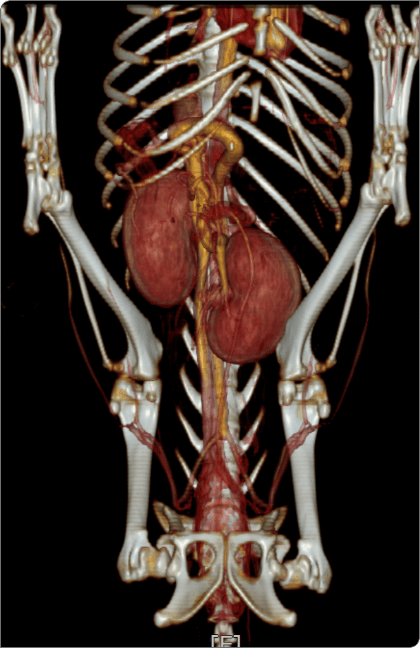

CT·심초음파 등 정밀 영상검사로 혈관 구조를 평가하고 수술 계획을 수립하며,

CT 혈관조영, 심장초음파 등 고사양 영상장비를 활용하여

혈관 구조와 병변을 정밀 분석, 최적의 수술 계획을 수립